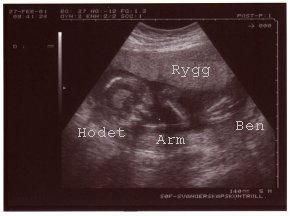

Ultralydsundersøkelse #3

Tirsdag 29.mai 2001 - tredje ultralydsundersøkelse. Denne gangen var det en ny jordmor. Det var rart å se nurket nå fordi han var blitt så stor. Jada...magefølelsen var rett. Det blir en liten gutt. *S* Liten og liten forresten. Han var ganske så stor. Skal tilbake til ul om fire uker for å ta en ny titt. Nyrene var ikke lenger dileterte og morkaken lå 10-15 cm over åpning. Plutten lå i seteleie, men det kan fremdeles endre seg mange ganger. *Krysser fingre for det* Det ble en lang seanse fordi det var en lege som også skulle sjekke nyrer o.l for sikkerhets skyld. Han begynte å titte på hjernen og lurte en stund på om det var litt for mye væske i de bakre hjernehalvdelene. Han kom frem til at det muligens var litt mer enn normalt så det skal også sjekkes opp neste gang. (Under vekstestimeringen). Fikk med to kjempefine bilder av nurket!